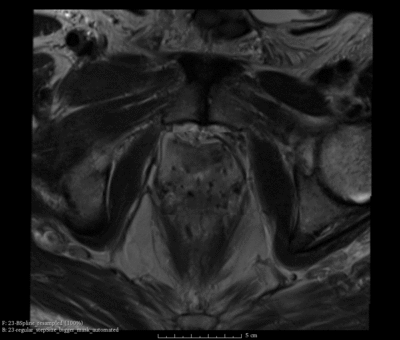

Case 25

High irregulations in ITKv4

Resolved Irregulations ins ITKv4

• Our registration module for b-spline deformable registration of prostate MRI uses BRAINSFit in Slicer4/ITKv4.

• One issue that we are getting with Slicer4/ITKv4 is that they are a lot more irregular and unrealistic than what we used to get in Slicer3/ITKv3 (see summary here)

• The Slicer4/ITKv4 registration tool should be comparable with the functionality we had in Slicer3/ITKv3, which was evaluated here